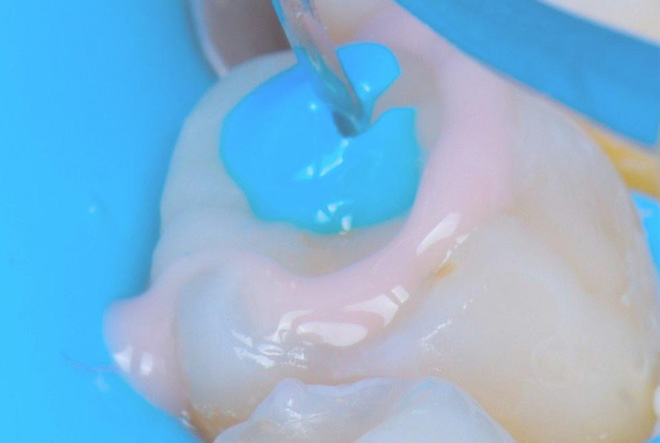

Case Study by Prof. Angelo Putignano: The best solution: One more overlay.

The step-luting technique optimizes the cementation of indirect restorations using dual-cure resin cement, addressing a critical…

The best solution: One more overlay.